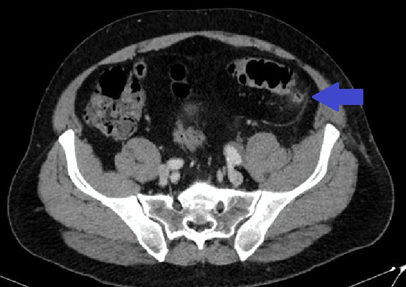

A 56-year-old man presented to the emergency department with a one week history of abdominal pain in the left lower quadrant with irradiation to the same side lumbar area. On the physical abdominal examination, he had localised tenderness in the left iliac fossa. Laboratory results showed white blood cell (WBC) count of 9.12 10e3/µL (4.00 - 12.00) and a C reactive protein (CRP) of 14.2 (<=5). A computed tomography (CT) scan was performed, which informed findings suggestive of epiploic appendagitis and multiple diverticula in the sigmoid colon (Figures 1, 2). The patient was sent home with conservative treatment.

Figure 1 Inflammatory appearance changes at the level of the epiploic appendage adjacent to the sigmoid colon. Axial plane.